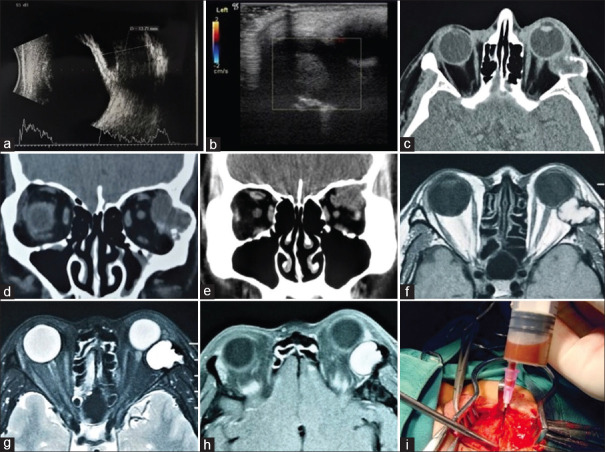

Results: The patients comprised 10 males and 2 females. The mean age was 34.5 years (standard deviation [SD] = 8.9, median: 36 and range: 16-45 years). Four patients had a history of orbital trauma. The clinical manifestations at the first visit were proptosis (7/12, 58.3%), periorbital or eyelid swelling (6/12, 50%), limitation of eye movement (4/12, 33.3%), ptosis (2/12, 16.7%), and decreased visual acuity (1/12, 8.3%). Computed tomography (CT) showed a nonenhancing, well-circumscribed lesion in the orbit with extensive erosion of the adjacent frontal bone and temporal bone. Magnetic resonance imaging (MRI) showed a nonenhancing mass with intermediate-to-high signal intensity on T1- and T2-weighted images. Ten patients underwent lateral orbitotomy, and two patients underwent supraorbital orbitotomy. All patients had aggressive bone erosion. Histopathologic evaluation of the cyst contents and wall revealed cholesterol clefts, multinucleated giant cells, histiocytes, foamy macrophages, and altered blood pigments. The mean follow-up time of 79.6 months (SD = 49.8, range: 19-193 months). Three patients were lost to follow-up. No postoperative diminution of vision was noted, and no recurrence was observed.

Conclusions: CGs can present as superotemporal or temporal orbital lesions. The diagnosis can be established based on CT and MRI. Most of the patients can have no history of orbital trauma.